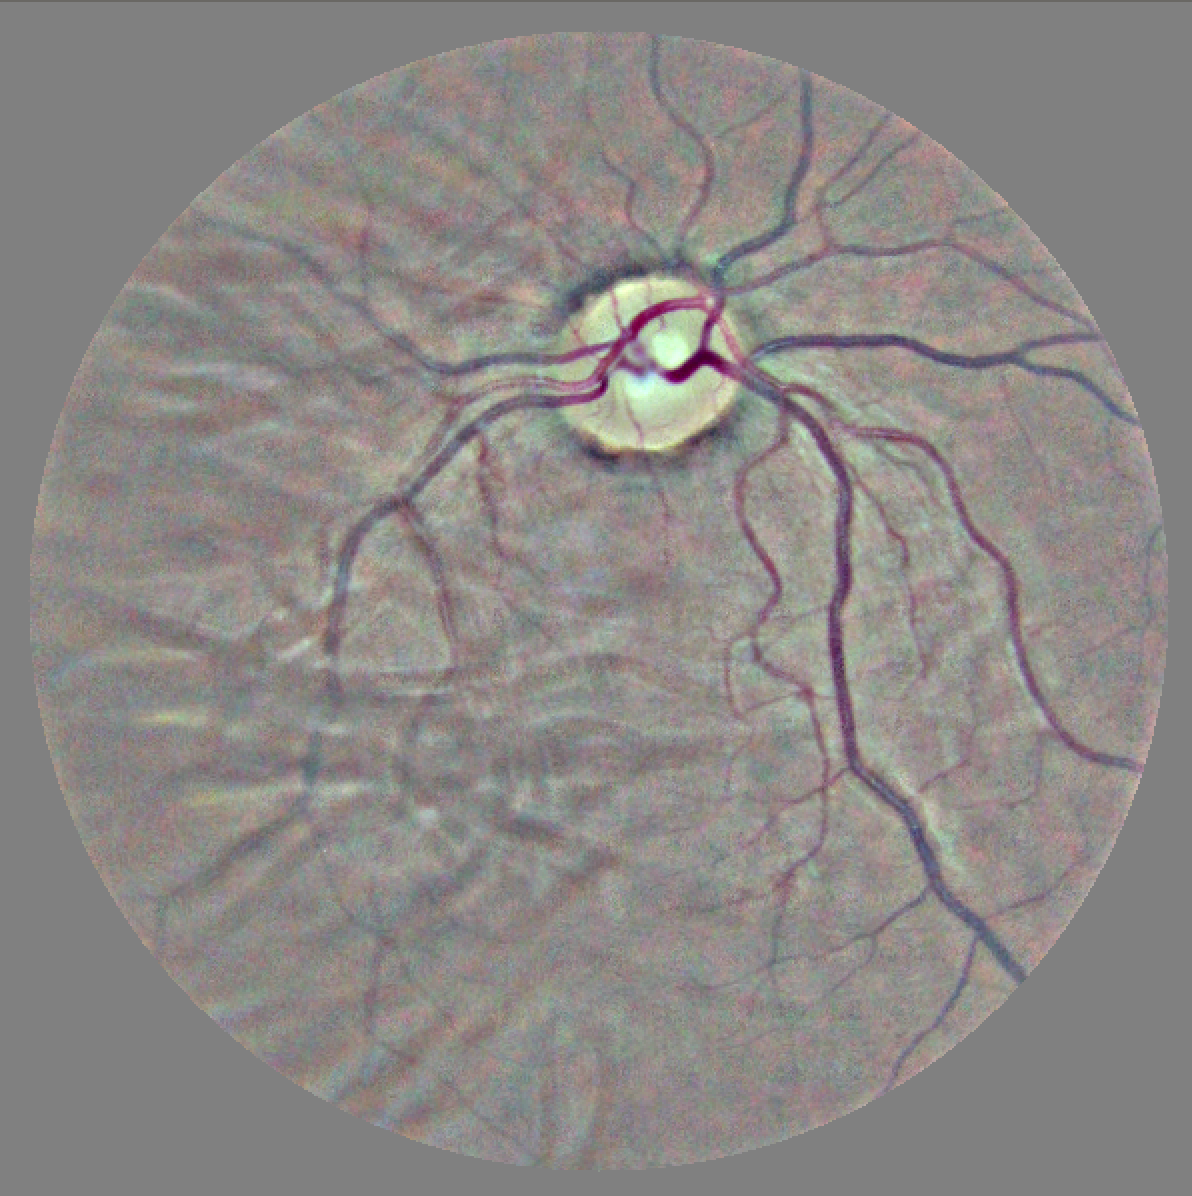

X-A Data

We chose the diabetic retinopathy dataset introduced by [32] both for its clinical impact and the privacy-sensitive nature of retinal data. The dataset consists of macula-centered retinal fundus images primarily sourced from EyePACS and was graded by 54 opthalmologists or opthalmologist trainees using the International Clinical Diabetic Retinopathy scale [7] into ‘none’, ‘mild’, ‘moderate’, ‘severe’, or ‘proliferative’ ratings for the severity of the condition.

We were able to obtain a subset of around 35,126 images of the dataset, with a label distribution of 25,810 ‘none’, 2,443 ‘mild’, 5,292 ‘moderate’, 873 ‘severe’, and 708 ‘proliferative’ diagnoses. Scans from both the left and right eye were sourced from each patient. To compare our results to the replication study performed by [66], we group the ‘none’ and ‘mild’ labels to a ‘0’ label and the ‘moderate’, ‘severe’, and ‘proliferative’ labels to a ‘1’ label to reframe our problem into a binary classification task. We randomly subsampled our dataset to get an even split between our two labels, and following the guidelines recommended by [32] we use an 80-20 split for training and test data.

Before using the retinal images with our network, we perform some preprocessing on the raw images. The scans are scaled to , the standard ImageNet input size, with cropping performed using edge detection to reframe the images. To normalize the colors and lighting, each image is subtracted by the local average color of each image, after which the local average is mapped to grayscale. Random rotation is performed on the image to make the model invariant to left/right eye positioning and for general augmentation. Samples of the data we use are provided in Figure 5.